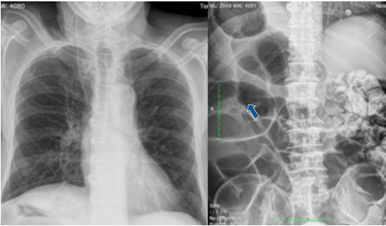

Se trata de un varón de 72 años, con antecedente de prostatectomía radical en 2019 por carcinoma de próstata, complicada con perforación iatrogénica de recto que requirió colostomía, con posterior reconstrucción del tránsito en un segundo tiempo quirúrgico. Se encontraba recibiendo radioterapia por recaída, cuando acude a urgencias por presentar dolor abdominal intenso, localizado en fosa iliaca derecha, asociado a cese de expulsión de heces y gases. Durante el examen físico al momento del ingreso el paciente se encontraba hemodinámicamente normal y estable, afebril, con abdomen distendido y timpánico, doloroso a la palpación profunda en hemiabdomen derecho. En el tacto rectal presentaba la ampolla rectal vacía. Se completó el estudio mediante analítica e imágenes diagnósticas, a saber: radiografía de tórax, que mostró ubicación cardíaca habitual con una discreta cardiomegalia, radiografía de abdomen, en la que se observaba marcada dilatación del marco cólico con ausencia de gas en ampolla rectal en relación con obstrucción intestinal (Figura 1), y tomografía (TC) abdominal, donde se informó situs inversus, marcada dilatación de ciego en hipocondrio derecho, con ingurgitación de vasos y signo del remolino, acompañado de hallazgos sugestivos de un patrón de oclusión a nivel de íleon distal, junto con líquido libre de localización perihepática, periesplénica y pélvica (Figura 2).